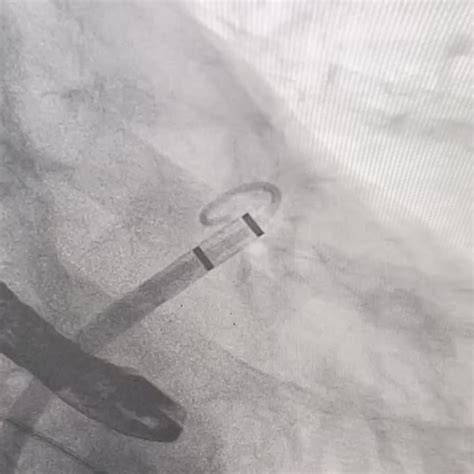

watchman leader  laac therapy boston scientific

watchman leader  laac therapy boston scientific 400×394